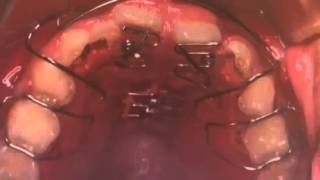

臨床医向けの床矯正と矯正治療に関する専門書。- 著者: 鈴木設矢- タイトル: 臨床医のための床矯正・矯正治療 反対咬合篇1度も読んでいない新品ですが素人の自宅保管になりますので、完璧な新品を求めている方は落札をご遠慮下さい。他にも多数出品しておりますので是非宜しくお願い致します。自己紹介文を必ず読んでから購入お願い致します。